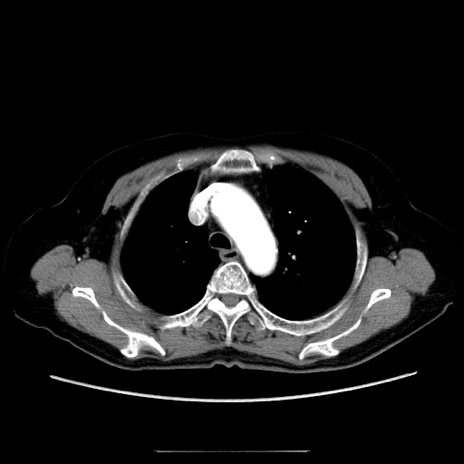

冠状断像